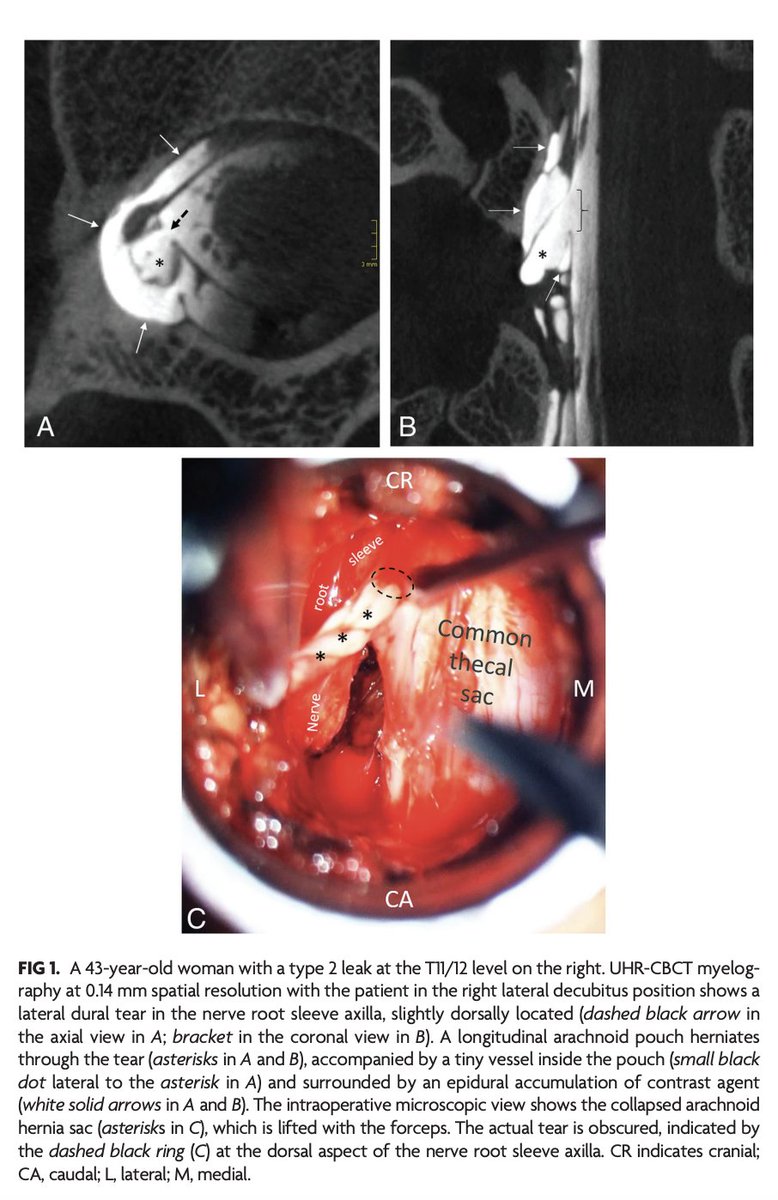

"Advanced Imaging of Type 2 Spinal CSF Leaks with Ultra-High-Resolution Conebeam CT Myelography" https://t.co/MeAXkyWHLb

@The_ASSR #CSFLeak